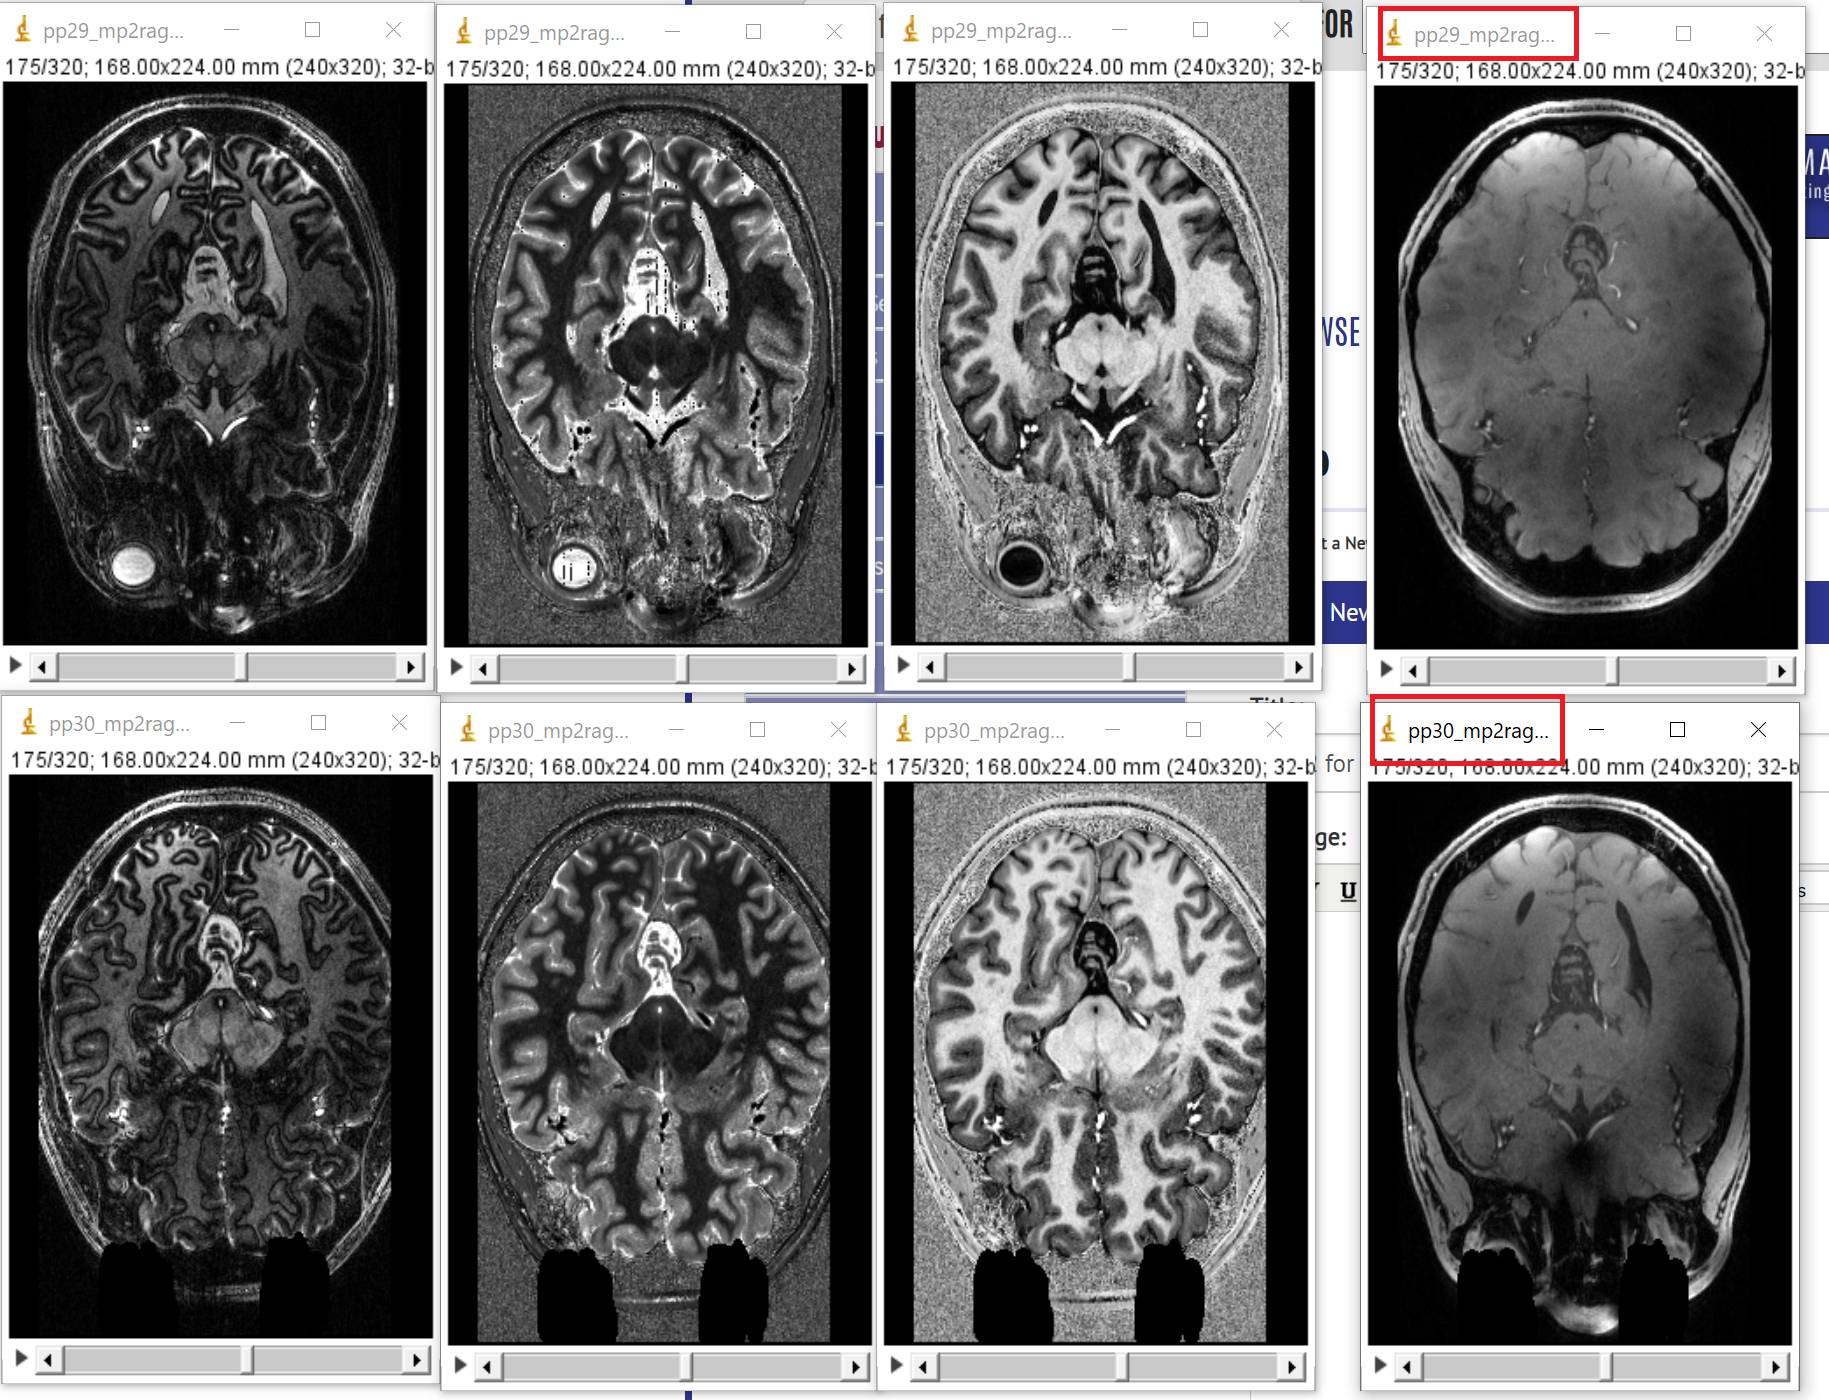

is it just me or are the image for the whole brain inversion2 swapped for subject 29 and 30 (see attachment)? The other (uni, t1, inv1) seem to be right.

Thank you for spotting this. It indeed seems to be the case that the name of the whole brain second inversion time has been swapped for subject 29 and subject 30. I'm sorry for any inconvenience this may have caused you. I have relabeled the files, updated the tar file on nitrc and dryad and added a note.